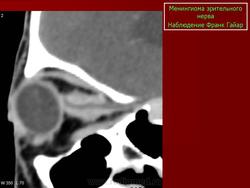

Наиболее типичная черта: объемное образование, расположенное вдоль интраорбитальной части зрительного нерва, накапливающее КВ и содержащее обызвествления по типу трамвайных рельс. Форма: тубулярная (65%) > на ножке (25%) > веретеновидная (10%). Формируется вокруг нерва, реже растет эксцентрично или имеет ножку

КТ-семиотика

На КТ срезах без контрастного усиления менингиома зрительного нерва выглядит изоденсной. Типично наличие линейных или точечных обызвествлений. Симптом «трамвайных рельс» отражает накопление КВ по сторонам гиподенсного зрительного нерва или наличие обызвествлений в структуре опухоли. Как правило, наиболее дистальная часть зрительного нерва, в месте его вхождения в глазное яблоко, не содержит обызвествлений.